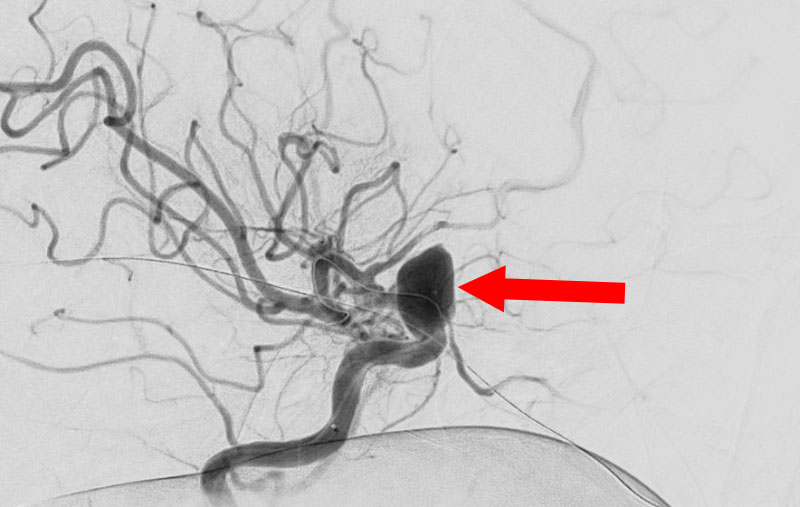

'25年11月

くも膜下出血

左中大脳動脈瘤破裂

40代

救急外来

No.1596 手術前

No.1596 手術中

No.1596 手術後